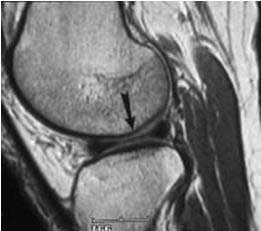

МРТ коленного сустава. Т2-взвешенная сагиттальная МРТ. Медиальный мениск в норме.

Важнейшую функцию амортизации (поглощения и перераспределения нагрузки), обеспечение стабильности, а также смазку и питание сустава выполняет мениск. Повреждения менисков чаще всего наблюдаются у спортсменов. Мениск представляет собой С-образную фиброзно-хрящевую структуру, прикреплённую к мыщелковым поверхностям большеберцовой кости. Концы «С» направлены к центру, верхняя поверхность мениска вогнутая, что улучшает контакт с головкой бедренной кости. Нижняя поверхность мениска плоская. При МРТ коленного сустава в сагиттальной плоскости видно, что наружная часть мениска выпуклая и толще центральной. Толстая внешняя часть мениска даёт возможность плотного его прилегания к суставной капсуле. У детей мениск имеет сосуды. Большая часть мениска у взрослых бессосудистое образование и только самая периферическая часть имеет сосуды. Высота мениска в норме 3-5 мм. Делится мениск на передний рог, тело и задний рог.

Медиальный мениск (ММ) больше латерального (ЛМ), имеет форму лунного серпа, занимает около 50% суставной поверхности медиального отдела сустава. Задний рог ММ толще заднего рога ЛМ. В ширину ММ от 6 мм в области переднего рога до 12 мм в области заднего рога. Поперечная (межменисковая) связка соединяет передние рога ММ и ЛМ. У 40% людей она отсутствует, что видно при МРТ коленного сустава.